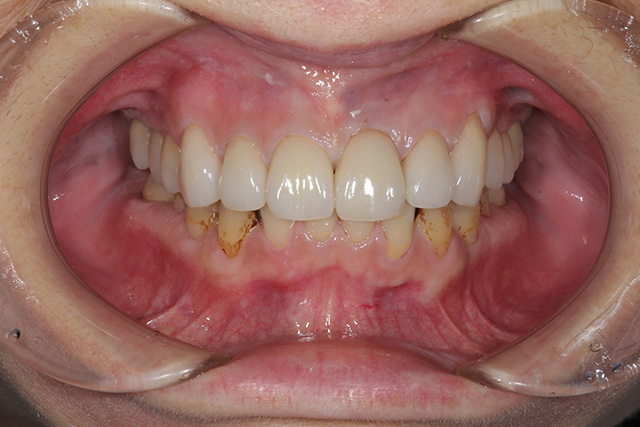

審美症例